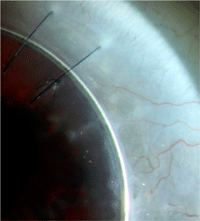

17 de los 27 injertos corneales (63%) permanecieron transparentes durante todo del seguimiento. En la mayoría de los injertos hubo una desviación de la invasión vascular en el injerto (89%) debido a la presencia del anillo de Krumeich (

Figura 3).

Figura 3. Imagen tomada de la lámpara de hendidura que muestra la desviación de los vasos por el anillo de Krumeich. Los nuevos vasos son desviados hacia la interfase donante-receptor dónde ejecutan su curso paralelamente y cerca del mismo anillo.